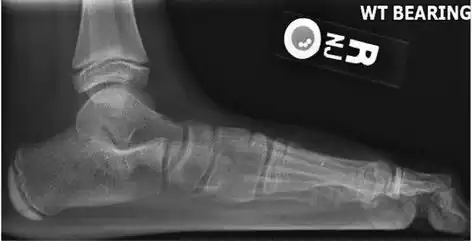

On plain radiography, flat feet can be diagnosed and graded by several measures, the most important in adults being the talonavicular coverage angle, the calcaneal pitch, and the talar-1st metatarsal angle (Meary's angle).[11] The talonavicular coverage angle is abnormally laterally rotated in flat feet.[11] It is normally up to 7 degrees laterally rotated, so a greater rotation indicates flat feet.[11] Radiographies generally need to be taken on weightbearing feet in order to detect misalignment.[12]

Weight-bearing lateral X-ray showing the measurement of calcaneal pitch, which is an angle of the calcaneus and the inferior aspect of the foot, with different sources giving different reference points.[13] A calcaneal pitch of less than 17° or 18° indicates flat feet.[11]

Same lateral X-ray showing the measurement of Meary's angle, which is the angle between the long axis of the talus and first metatarsal bone.[11] An angle greater than 4° convex downward is considered a flat foot, 15° - 30° moderate flat foot, and greater than 30° severe flat foot.[11]